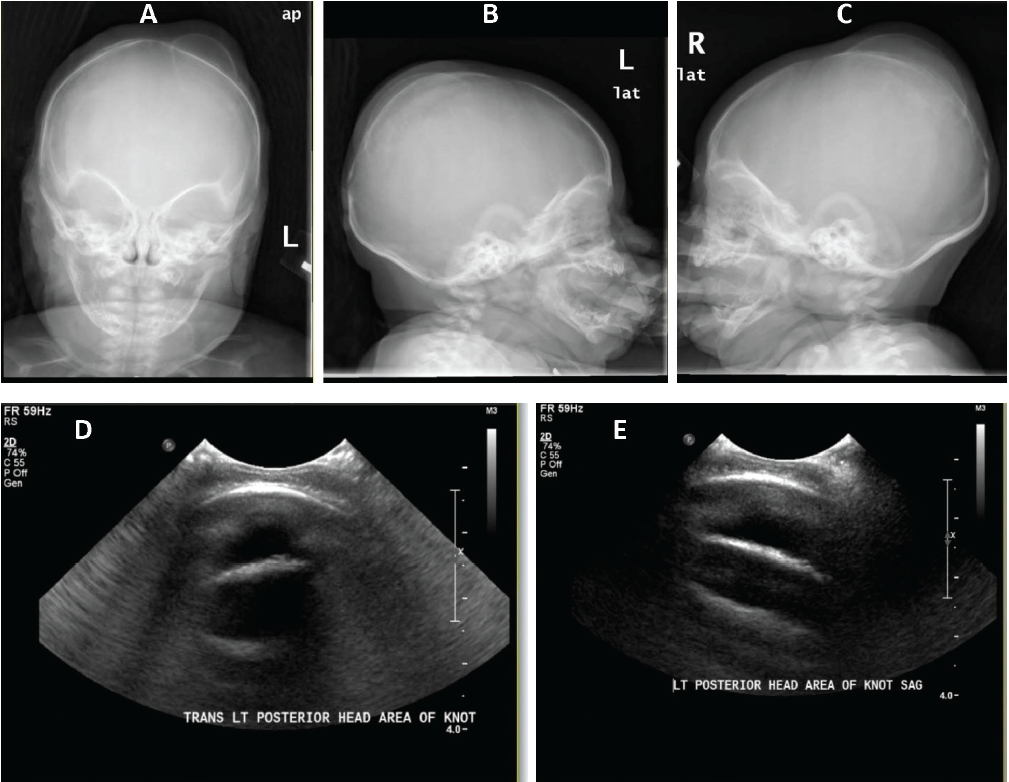

cephalohematoma

01/06/2016

Bhargavi B. Kola, MD, MPA; Vivekananda Dasari, MD; Theresa T. Phan, BS

A 4-month-old boy presented with a 2.5 × 6.0-cm bony mass in the left parietal region.